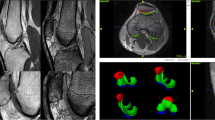

GE sequences are used for optimal imaging of menisci, articular cartilage, labrum and ligaments. Three-dimensional (volume) acquisitions can also be obtained using GE, particularly useful in small joints such as the wrist (Fig. 7.5). Other advantages include the increased conspicuity of haemorrhage, haemosiderin-laden synovium in pigmented villonodular synovitis (PVNS) (Fig. 7.5c), loose bodies or gas. Thin section fat-suppressed gradient echo sequences have been shown to be more sensitive than fat-suppressed T1-weighted images for detecting labral tears in direct arthrography of the shoulder. T1W sequences were more specific in delineating the tears, suggesting the need for multisequence imaging (Lee et al. 2008).

Gradient echo sequence. (a) Image of the wrist, demonstrating the scapholunate ligament (arrow). (b) Axial image of the glenohumeral joint demonstrating articular cartilage (arrow). (c) Gradient echo T2* axial image through the patellofemoral joint showing hypointense synovial thickening in a patient with diffuse PVNS (arrow)

Disadvantages of GE sequences include increased metallic artefact, poor demonstration of marrow pathology in the absence of trabecular destruction and overestimation of the size of osteophytes in the spine (Helms et al. 2009).

Typical parameters for GE T1 sequence: TE variable, TR < 30, flip angle 70–110

Typical parameters for GE T2* sequence: TE variable, TR < 30, flip angle 5–20 (Helms et al. 2009).

Sodium Spectroscopy: Proteoglycans and collagen are important constituents of articular cartilage. Loss of proteoglycans results in failure of the articular cartilage, leading to chondral thinning, chondromalacia and arthritis.

Proteoglycans have a net negative charge, which attract positively charged sodium ions (Shapiro et al. 2000; Borthakur et al. 2000). As a result, the amount of articular cartilage present can be indirectly measured by evaluating sodium ion concentration using sodium spectroscopy. Abnormalities in the articular cartilage can be identified before any pathology is identified with standard MRI. This technique is also useful for evaluating the success of chondral and osteochondral implants. Different RF coils and imaging protocols are required for sodium spectroscopy.